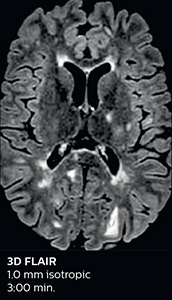

Ingenia Elition 3.0T with Compressed SENSE

3D FLAIR 1.0 x 1.0 x 1.0 mm* 2:50 min.

*true voxel size, without interpolation

The abbreviated MS protocol for brain is only around 9 minutes, so in case of suspected multiple sclerosis, one or two more advanced sequences may be added, such as PSIR (phase sensitive inversion recovery) or susceptibility-weighted sequences to help us make more confident diagnoses in these inflammatory cases.

In this example, the optional 3D multishot susceptibility weighted sequence with 0.6 mm isotropic voxels is 2 lesions with a central vein sign (arrows) and one lesion with a phase-rim sign (arrowhead). The total scan time, including SmartBrain and axial PD/T2 3mm, is 11:10 min. and is 18:30 min. with the optional 3D PSIR and 3D SWI multishot included.

“We used to have long examination times for certain types of patients, a few lasting more than 40 minutes,” says Dr. Savatovsky. “What is remarkable, is that now all these examinations are below 30 minutes, which opens up opportunity to add more sequences when needed. It’s really hard to keep a patient for more than 40 minutes in the scanner, but because we have now cut scan times by at least 10 minutes, we can add more sequences without making the exam too long. And this is where the new system helps us make a difference. Examples include our examinations for informing brain tumor classification or giant cell arteritis workup, or for intracranial wall imaging – so in patients where we need several advanced sequences or high resolution sequences.” “We added three additional sequences in our brain neoplasm classification exam: a 3D SWI sequence, APT and ASL on top of 3D morphologic sequences, an isotropic DSC (dynamic susceptibility contrast) and multivoxel spectroscopy. I think that in patients that need a classification for brain mass, for example, we can provide a more detailed and confident diagnosis than before, allowing the clinicians to decide for either a medical workup if no tumor is suspected, or for neurosurgery as soon as possible if a neoplasm is suspected.” “In multiple sclerosis patients, we increasingly include a multishot susceptibility sequence [3] in our routine cases, thanks to the shorter scan times. Our abbreviated MS protocol for brain is around 8 to 9 minutes, so we can ask for one or two additional sequences to visualize the central veins, or to get an additional contrast to better depict posterior fossa lesions. In cases of white matter lesions of unknown significance on FLAIR images, for example when we see high signal hyperintensities in the brain, we can add on more advanced sequences such as PSIR (phase sensitive inversion recovery) or susceptibility-weighted sequences to help us in distinguishing between MS and nonspecific or vascular abnormalities in these inflammatory cases.”